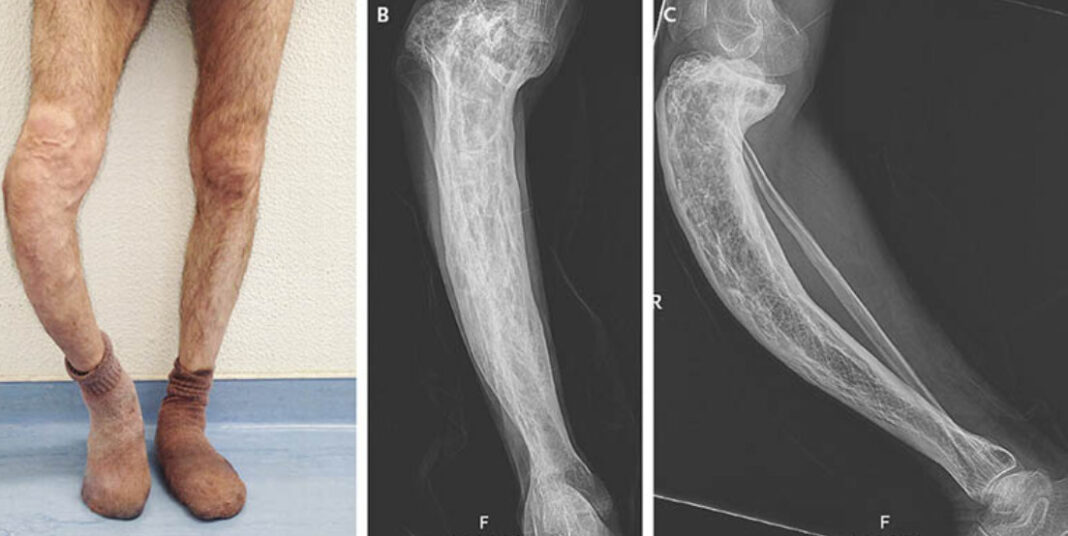

- Xương chân: xương chân có thể bị uốn cong do bị Paget. Người bệnh sẽ có triệu chứng là chân vòng kiềng, khi xương to ra, biến dạng sẽ càng làm tăng áp lực cho những vùng khớp lân cận. Theo thời gian khớp xương ở hông và đầu gối sẽ gặp phải tình trạng viêm.

Kiểm tra hình ảnh

Thông thường, kết quả chụp X – quang sẽ cho thấy các dấu hiệu bất thường đầu tiên của bệnh paget. Hình ảnh xương có thể biểu hiện các khu vực tái hấp thu xương, mở rộng và biến dạng xương; đó là các đặc trưng của bệnh Paget.

Ngoài ra, bác sĩ có thể thực hiện chiếu xương. Bệnh nhân sẽ được tiêm chất phóng xạ vào người để thực hiện bước kiểm tra hình ảnh này. Các chất phóng xạ đi đến các điểm xương bị ảnh hưởng nhất của bệnh paget và hiển thị điểm sáng lên những hình ảnh.